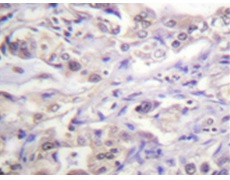

IHC positive control: |

Human lung carcinoma tissue |